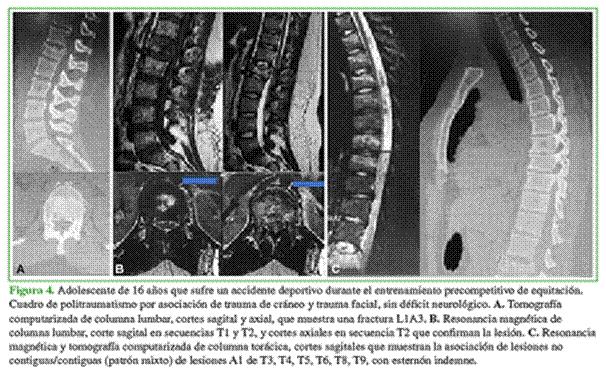

Las lesiones asociadas eran contiguas (32 casos), no contiguas (19 casos) o tenían un patrón mixto (contigua/no contigua) (15 casos) (Figuras 3 y 4).

Introducción: Las fracturas vertebrales múltiples son el resultado de traumatismos de alta energía. Se clasifican en contiguas cuando hay fractura de dos o más cuerpos vertebrales en forma adyacente y no contiguas cuando hay lesiones de varios niveles separadas por, al menos, una vértebra sin lesión. Objetivos: Evaluar la clínica y la cinemática de las fracturas vertebrales múltiples, establecer su distribución, evaluar la asociación con lesiones extravertebrales y detallar las complicaciones. Materiales y Métodos: Estudio multicéntrico, prospectivo y observacional de pacientes con fracturas vertebrales múltiples. Resultados: 66 pacientes (26 mujeres y 40 hombres; promedio de edad 39 años) con 196 lesiones vertebrales, 55 no tenían déficit neurológico. Cinemática: 32 accidentes automovilísticos, 27 caídas de altura, 5 traumas directos y 2 traumas deportivos. Topografía: dos C0-C3, cuatro C3-C7, ocho C7-T1, 61 T1-T10, 91 T10-L2, 28 L2-L5 y una sacro. Combinación: 21 toracolumbar-toracolumbar y 8 torácica-torácica. Treinta y dos fracturas eran contiguas; 19, no contiguas y 15 tenían un patrón mixto. Veintiséis pacientes presentaron 47 lesiones extravertebrales (20 politraumatismos), 12 traumas torácicos. Treinta y seis pacientes recibieron tratamiento conservador y 30 fueron operados. Conclusiones: La presencia de fracturas vertebrales múltiples es frecuente y son consecuencia de accidentes automovilísticos, la mayoría de los pacientes no tiene compromiso neurológico. El sector más afectado fue entre T2 y L5, la combinación más frecuente fue toracolumbar-toracolumbar, seguida de torácica-torácica. Las lesiones extravertebrales más frecuentes fueron traumatismos de cráneo y de tórax.